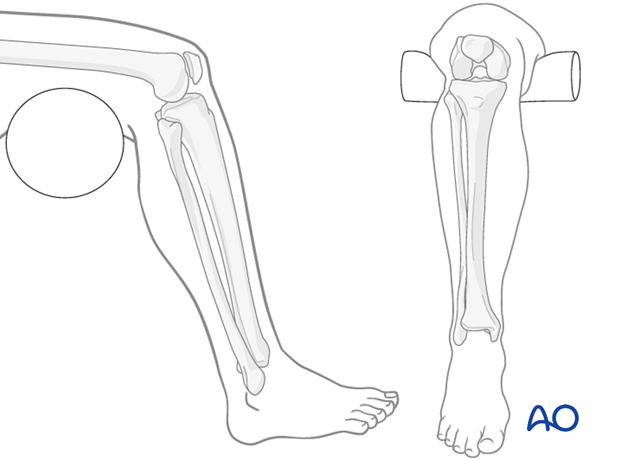

The surgeon is seated on a low chair. The patient’s knee is flexed over the end of the table; the thigh is supported with padding.

The patient sits on the edge of a table. The foot is steadied.